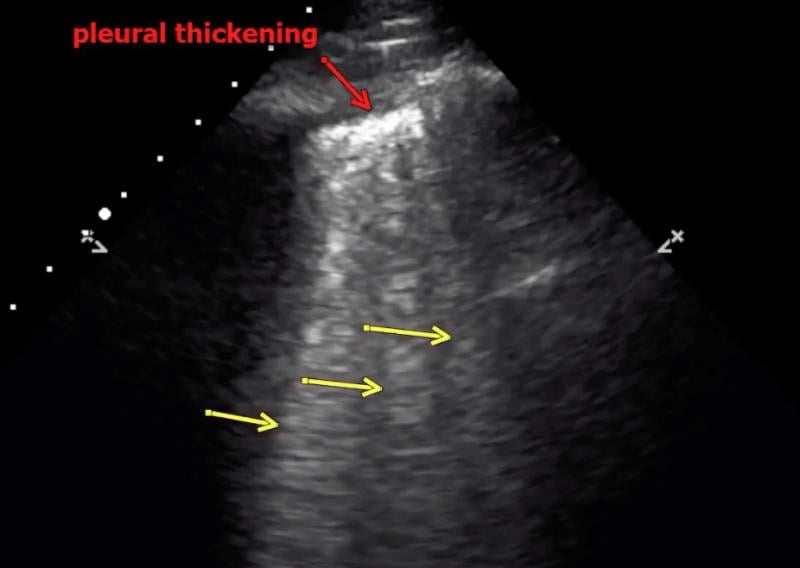

This photo gallery shows the variety of radiological presentations of COVID-19 (SARS-CoV-2) in medical imaging, including computed tomography (CT), radiograph X-rays, ultrasound, echocardiograms and magnetic resonance imaging (MRI). The radiology images show examples of typical COVID pneumonia in the lungs and the numerous complications the virus causes in the body in multiple organs, including the brain, kidneys, heart, abdomen and vascular system.

Ultrasound, especially hand-held ultrasound imaging devices, have become a primary imaging modality for novel coronavirus because of the ease to bag the device and sterilize it after use. CT and mobile X-ray systems are also used as front-line imaging systems for COVID-positive or suspected COVID patients.